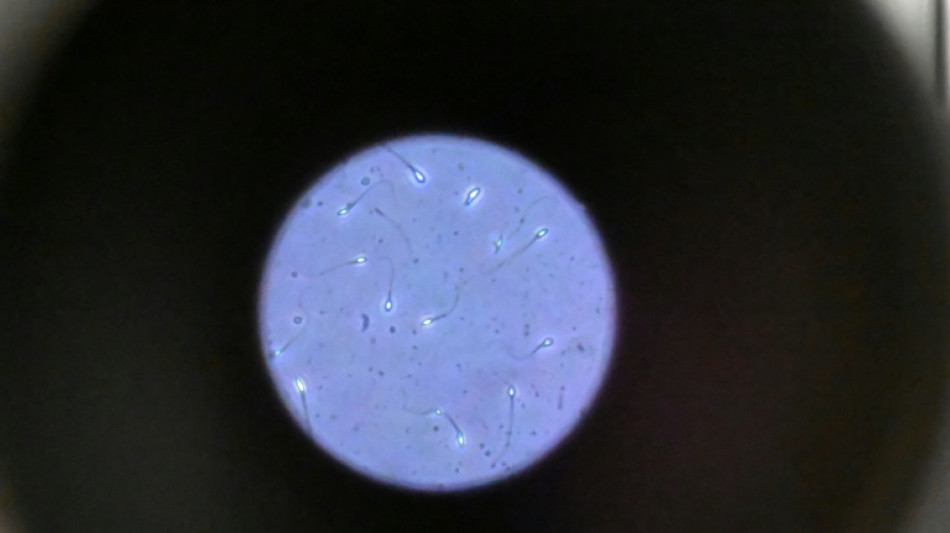

Dans l'espace, les spermatozoïdes ont du mal à trouver leur chemin

Dans l'espace, les spermatozoïdes ont du mal à trouver leur chemin / Photo: Damien MEYER - AFP/Archives

Dans l'espace, les spermatozoïdes ont du mal à trouver leur chemin vers l'ovule en raison de la microgravité, qui perturbe aussi le développement des embryons, selon une étude publiée jeudi dans Communications Biology.

"Les spermatozoïdes doivent activement trouver leur chemin vers l'ovule et cette étude est la première à tester leur capacité à le faire dans des conditions semblables à ce qui se passe dans l'espace", explique à l'AFP Nicole McPherson, autrice principale de l'étude et chercheuse à l'Université d'Adelaïde (Australie).

Son équipe a utilisé une chambre en plastique imitant l'appareil génital féminin, qui leur a servi de "parcours d'obstacles miniature". "Voyez ça comme un minuscule circuit de course... Les spermatozoïdes étaient introduits à une extrémité et devaient nager jusqu'à l'autre bout", décrit-elle.

Les chercheurs ont testé successivement du sperme de souris et humain dans ce dispositif placé dans un appareil en constante rotation pour simuler la microgravité.

Les gamètes ont été environ 50 % moins performants pour naviguer à travers ce parcours que sous la gravité terrestre. Cela équivaut à une baisse de 30% du taux de fécondation réussie, selon les résultats de l'étude.

Les spermatozoïdes ayant réussi à franchir le parcours semblaient produire des embryons de meilleure qualité.

Il semble que le stress lié à la microgravité ait agi comme un "filtre" éliminant les plus faibles et "ne laissant en lice que les plus performants", ce qui pourrait s'avérer "bénéfique", selon Mme McPherson.

Cependant, un problème plus important est apparu dans les vingt-quatre heures suivant la fécondation.

"Les résultats se sont brutalement inversés, avec moins d'embryons formés. Et ceux qui restaient étaient de moins bonne qualité", note la chercheuse.

La microgravité "n'est peut-être pas l'obstacle insurmontable que nous craignions, mais protéger les embryons de l'impesanteur au cours de ces premières heures critiques sera vraisemblablement essentiel pour la reproduction dans l'espace", avance Mme McPherson.

De nombreuses autres recherches seront cependant nécessaires pour comprendre comment la reproduction fonctionne dans l'espace, la fécondation n'étant qu'une "petite pièce d'un très grand et complexe puzzle", ajoute-t-elle. "Nous sommes encore très loin de voir un premier bébé de l'espace"!